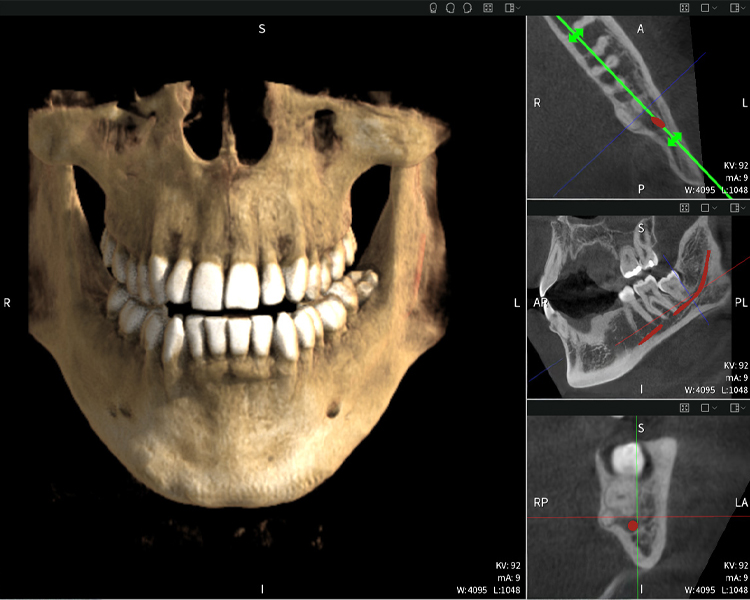

Below you will find a case from Dr. med. dent. Oliver A. Centrella, in which the CBCT images obtained with Seethrough Max provided crucial information on the complex anatomy and the critical relationship between the wisdom teeth and the inferior alveolar nerve. In this case, there is a indication for the surgical removal of the wisdom teeth.

Figure a: Imaging results of Seethrough Max, in front of a black background.

Figure a

• Top left: Axial cross-section of the left mandible (region 38) showing the inferior alveolar nerve (red) in proximity to the roots of tooth 38.

• Top right: 3D reconstruction of the entire mandible for orientation. The red-marked inferior alveolar nerve illustrates its location within the jawbone.

• Bottom left: Sagittal view of the mandible (region 38), highlighting the close spatial relationship between the roots and the nerve canal.

• Bottom right: Coronal view of the mandible (region 38), which is crucial for assessing the spatial position of the roots relative to the nerve.